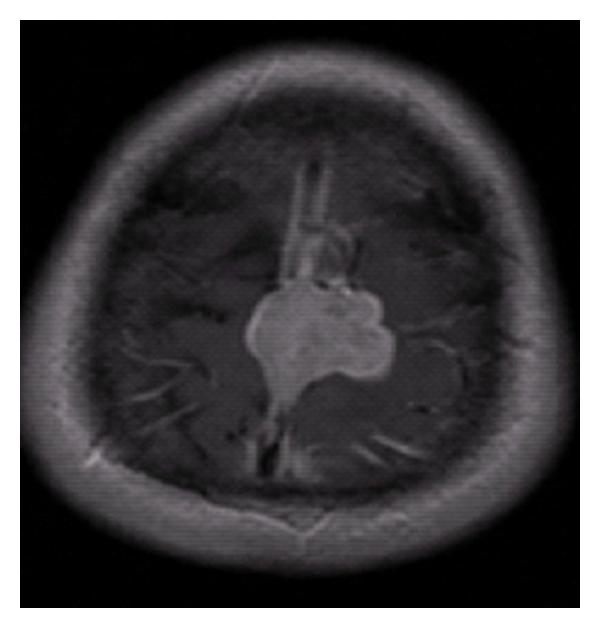

Primary meningeal rhabdomyosarcoma is a rare primary brain malignancy, with scant case reports. While most reports of primary intracranial rhabdomyosarcoma occur in pediatric patients, a handful of cases in adult patients have been reported in the medical literature. We report the case of a 44-year-old male who developed primary meningeal rhabdomyosarcoma. After developing episodes of right lower extremity weakness, word finding difficulty, and headaches, a brain magnetic resonance imaging (MRI) demonstrated a vertex lesion with radiographic appearance of a meningeal-derived tumor. Subtotal surgical resection was performed due to sagittal sinus invasion and initial pathology was interpreted as an anaplastic meningioma. Re-review of pathology demonstrated rhabdomyosarcoma negative for alveolar translocation t(2;13). Staging studies revealed no evidence of disseminated disease. He was treated with stereotactic radiotherapy with concurrent temozolamide to be followed by vincristine, actinomycin-D, and cyclophosphamide (VAC) systemic therapy.

原发性脑膜横纹肌肉瘤是一种罕见的原发性脑恶性肿瘤,病例报告较少。虽然大多数原发性颅内横纹肌肉瘤的报告发生在儿科患者中,但医学文献中也报道了少数成年患者的病例。我们报告了一例44岁男性原发性脑膜横纹肌肉瘤的病例。在出现右下肢无力、找词困难和头痛症状后,脑部磁共振成像(MRI)显示顶部有一个病变,影像学表现为脑膜来源的肿瘤。由于矢状窦受侵,进行了次全手术切除,初始病理诊断为间变性脑膜瘤。病理复查显示为横纹肌肉瘤,肺泡转位t(2;13)阴性。分期检查未发现播散性疾病的证据。他接受了立体定向放疗并同时使用替莫唑胺,随后接受长春新碱、放线菌素-D和环磷酰胺(VAC)全身治疗。